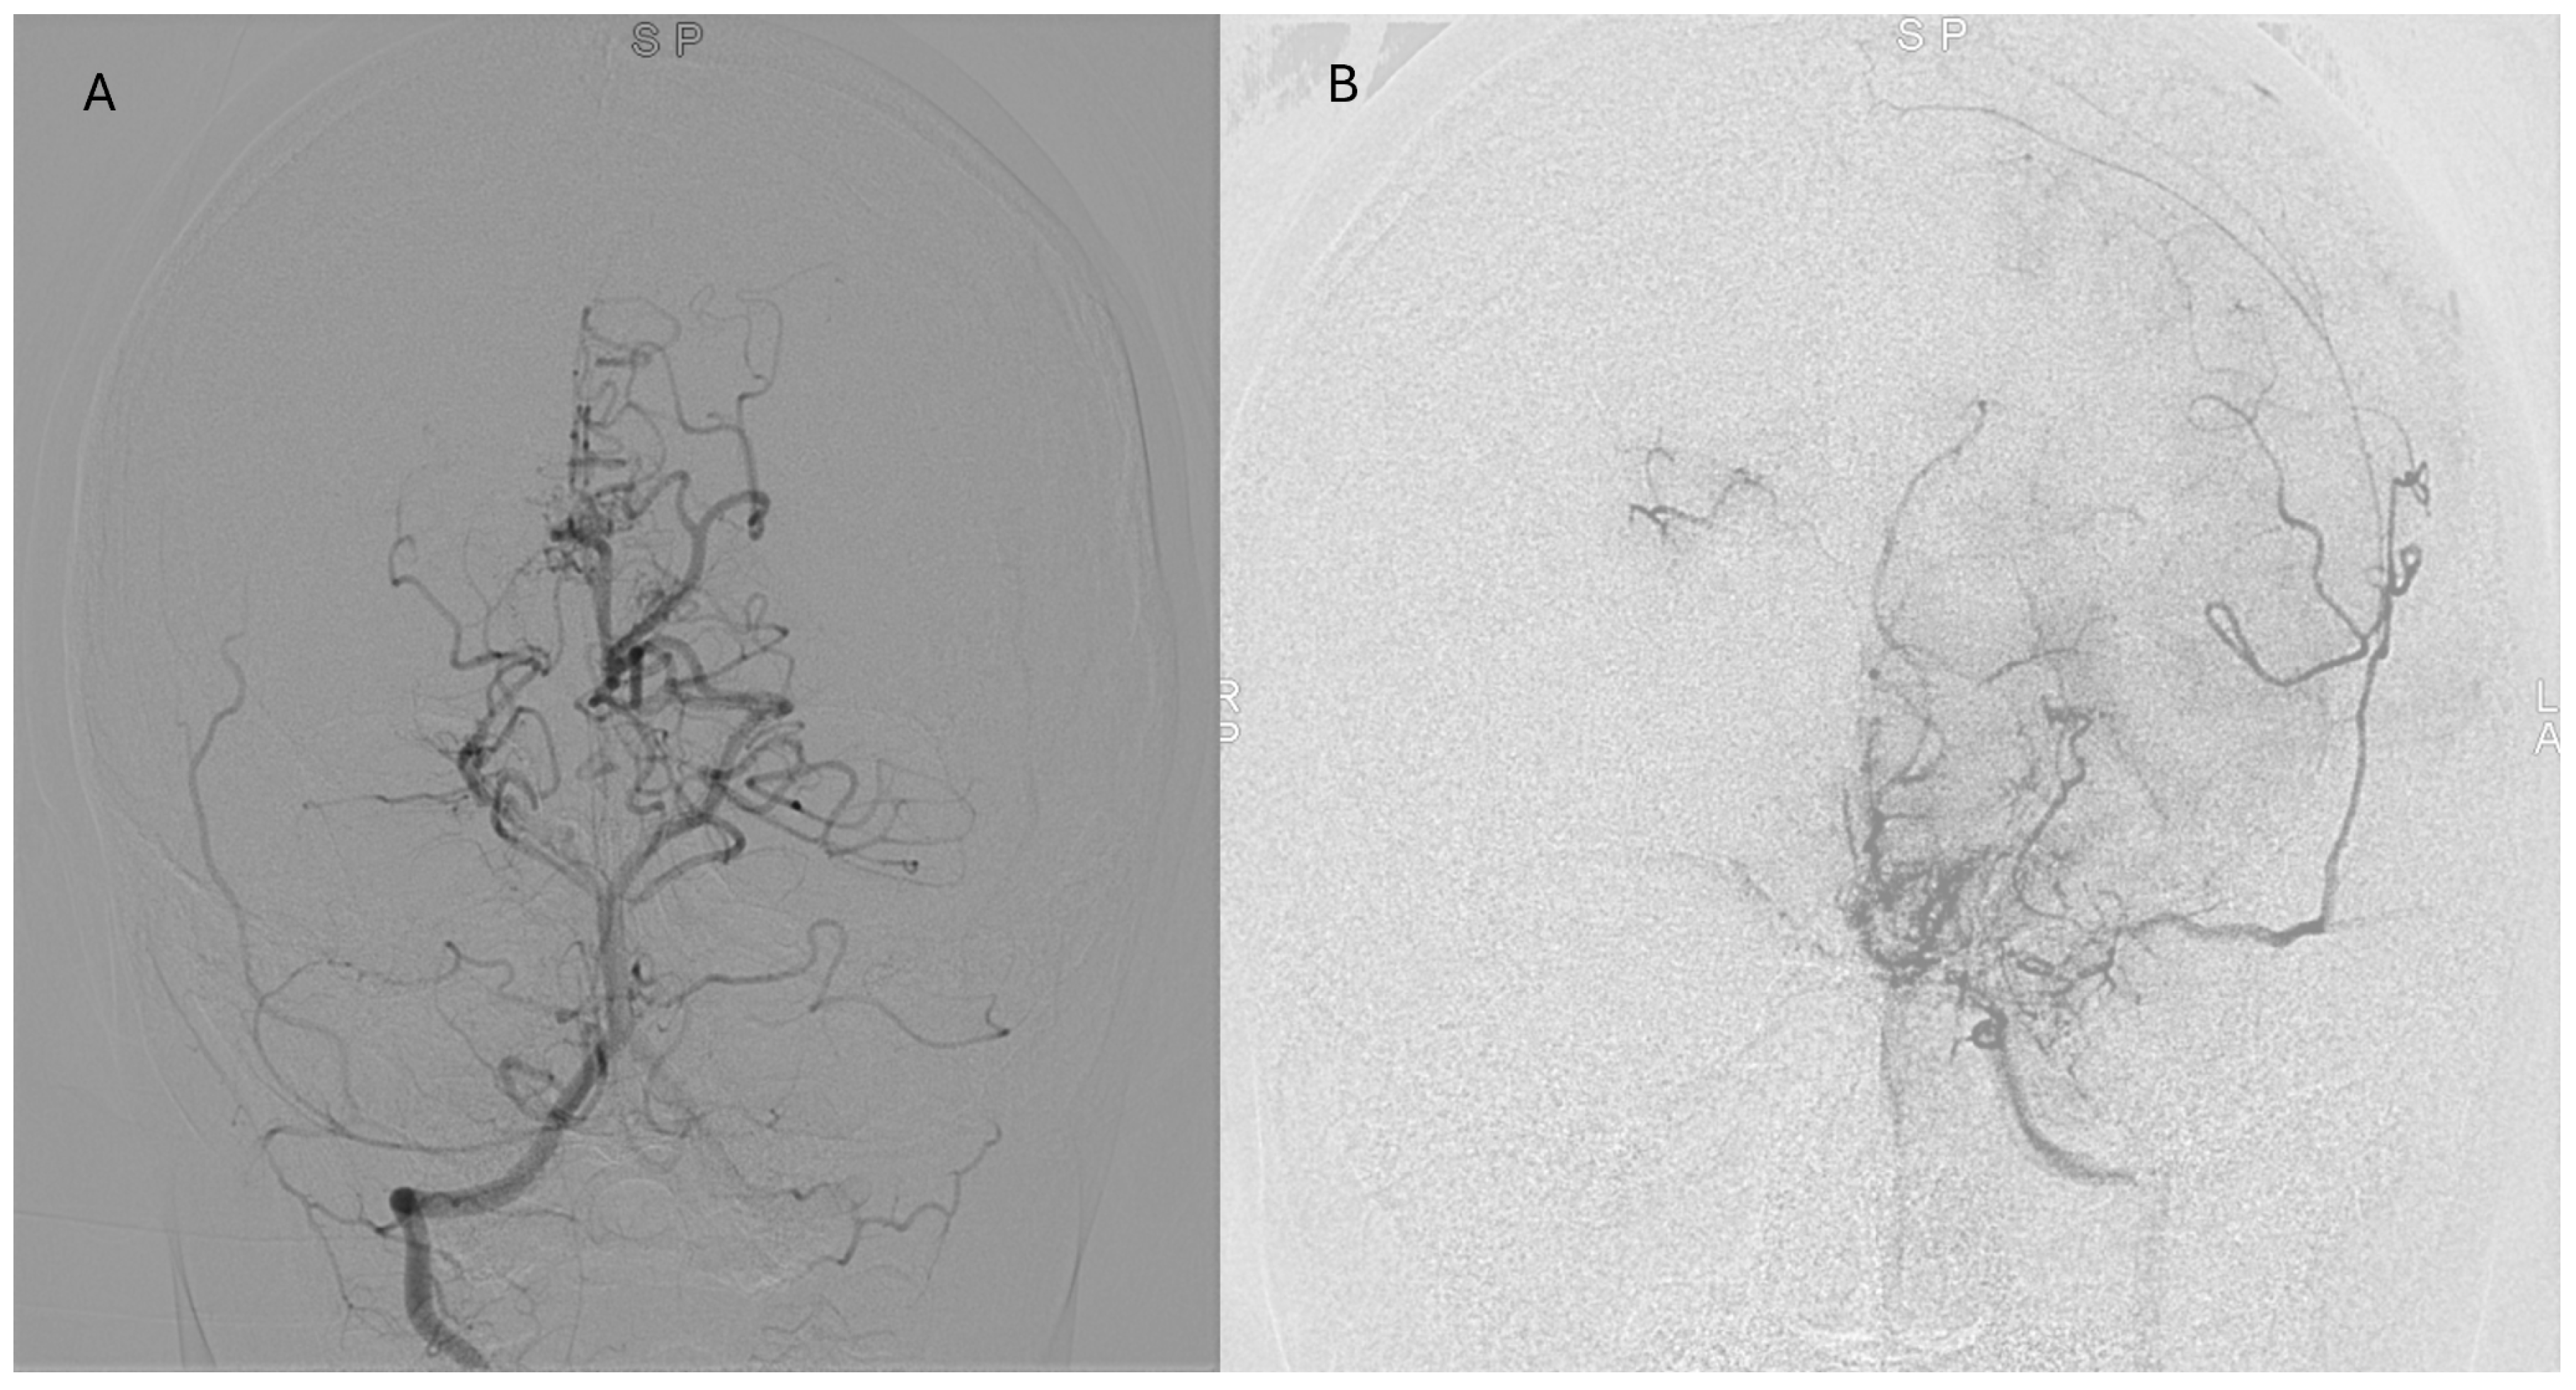

Representative postoperative angiographic images are shown in

Figure 1,

Figure 2 and

Figure 3. The mean operative time was 3.2 h and the average length of hospital stay was 7 days. All patients were monitored in the pediatric intensive care unit for 24–48 h before being transferred to the ward.

Postoperative angiographic follow-up was available for all revascularized hemispheres (n = 14). Examinations were typically performed at 3–6 months after surgery and repeated at 12–18 months in selected cases with persistent or recurrent symptoms. According to the Matsushima grading system, six hemispheres (43%) achieved grade A and 8 (57%) grade B collateralization, with no cases classified as grade C. Patients who developed grade A/B collaterals demonstrated parallel improvement in functional outcomes, with a median postoperative mRS of 1 compared to 2 preoperatively. Although the sample size precluded formal correlation testing, this qualitative relationship reinforces the functional impact of successful indirect revascularization on cerebral perfusion and recovery.